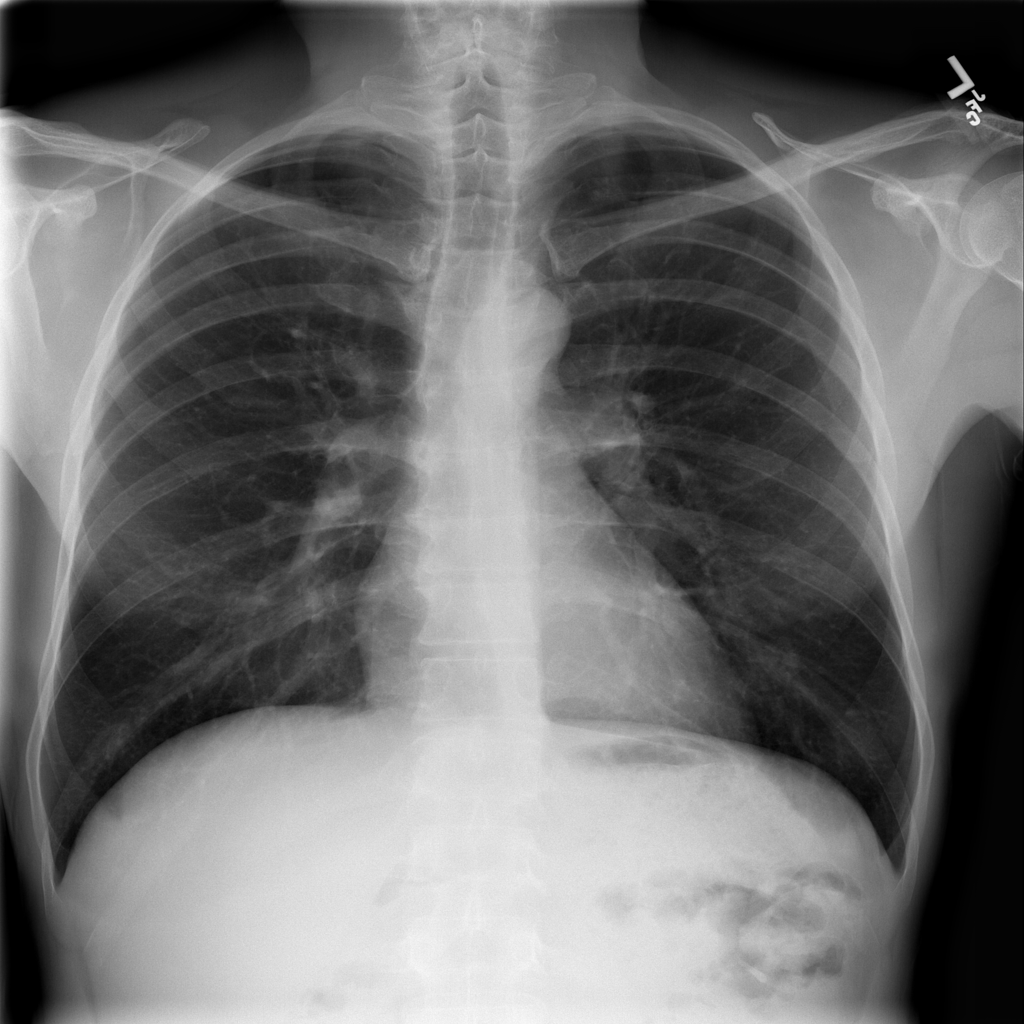

Showing up to 90 reference images for Pneumonia.

PAT-EBE1 · IMG-019Pneumonia

PAT-EBE1 · IMG-019

AP